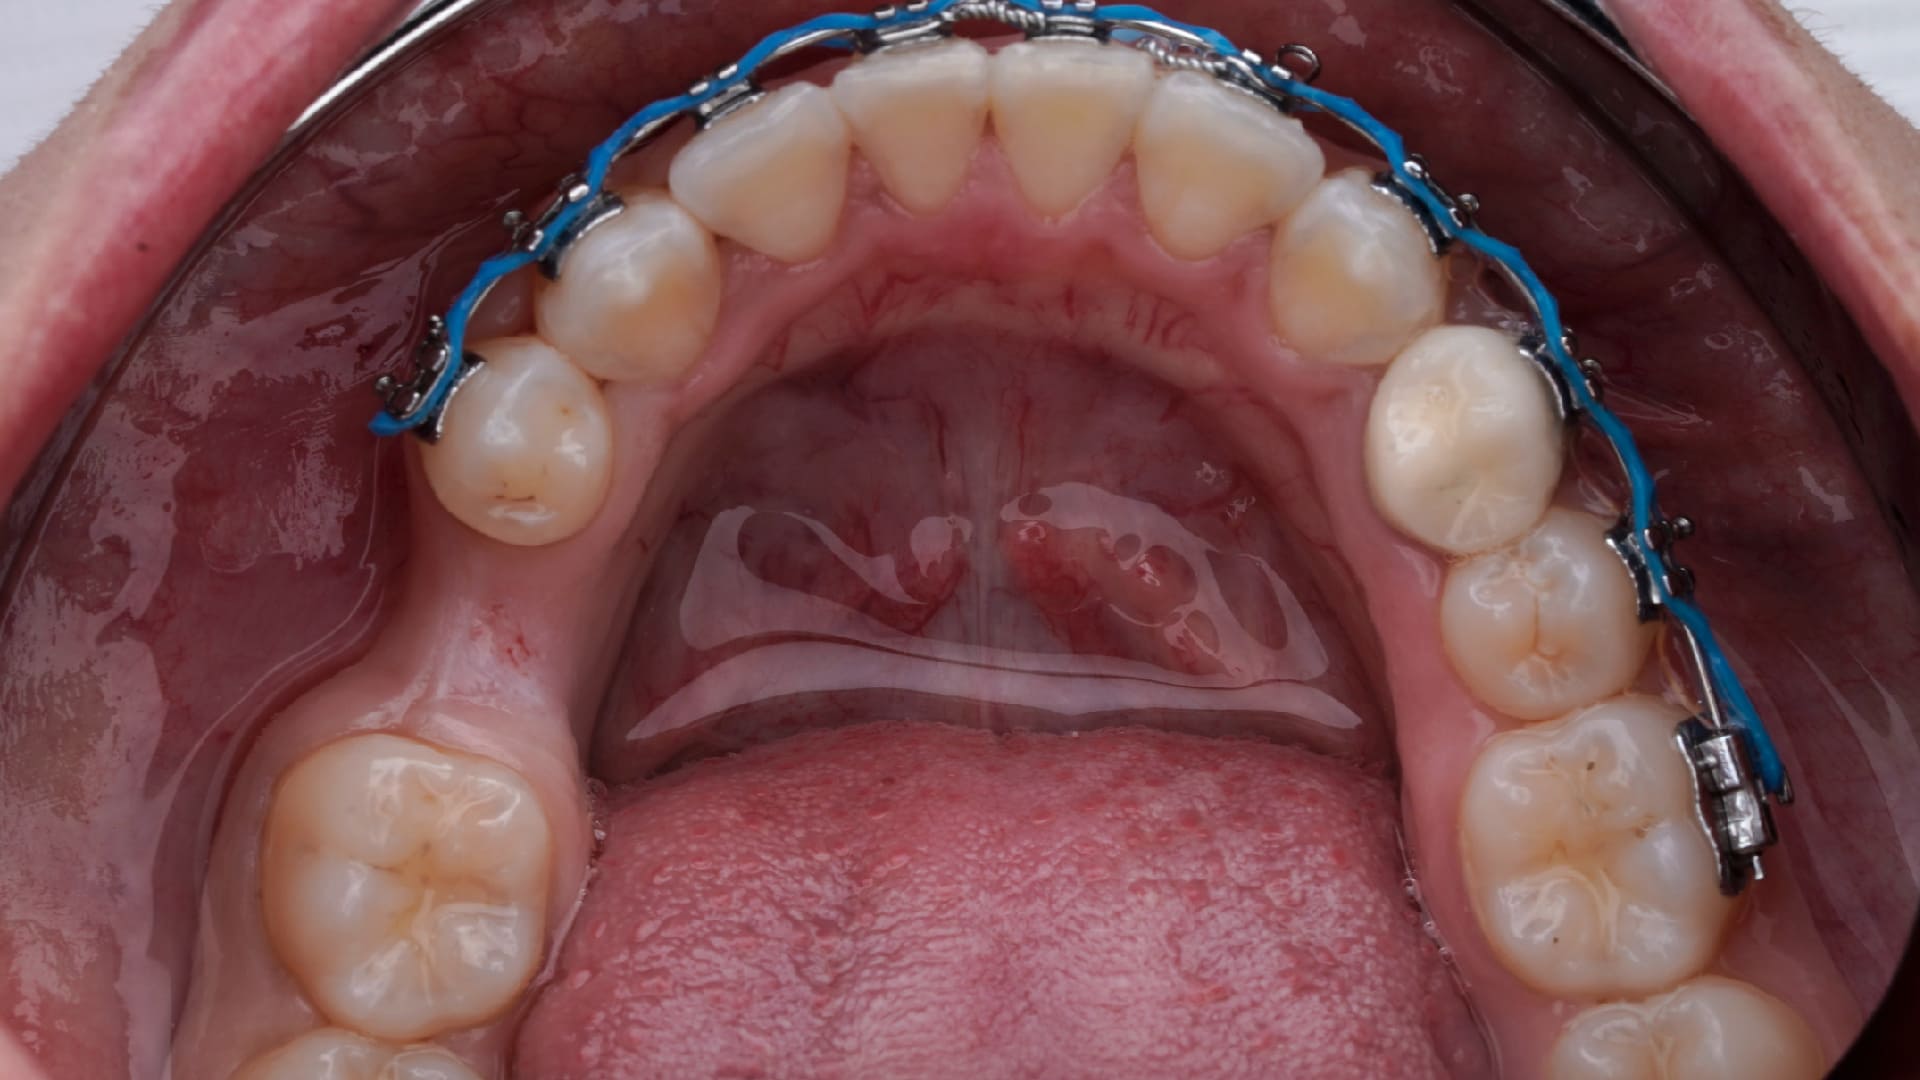

Treatment options to gain KT around Teeth and Implant

FGG around teeth

FGG to augment the KT and Vestibuloplasty;

Soft tissue graft around implants

Learn the importance of the KT and master the technique to create KT around teeth and implant